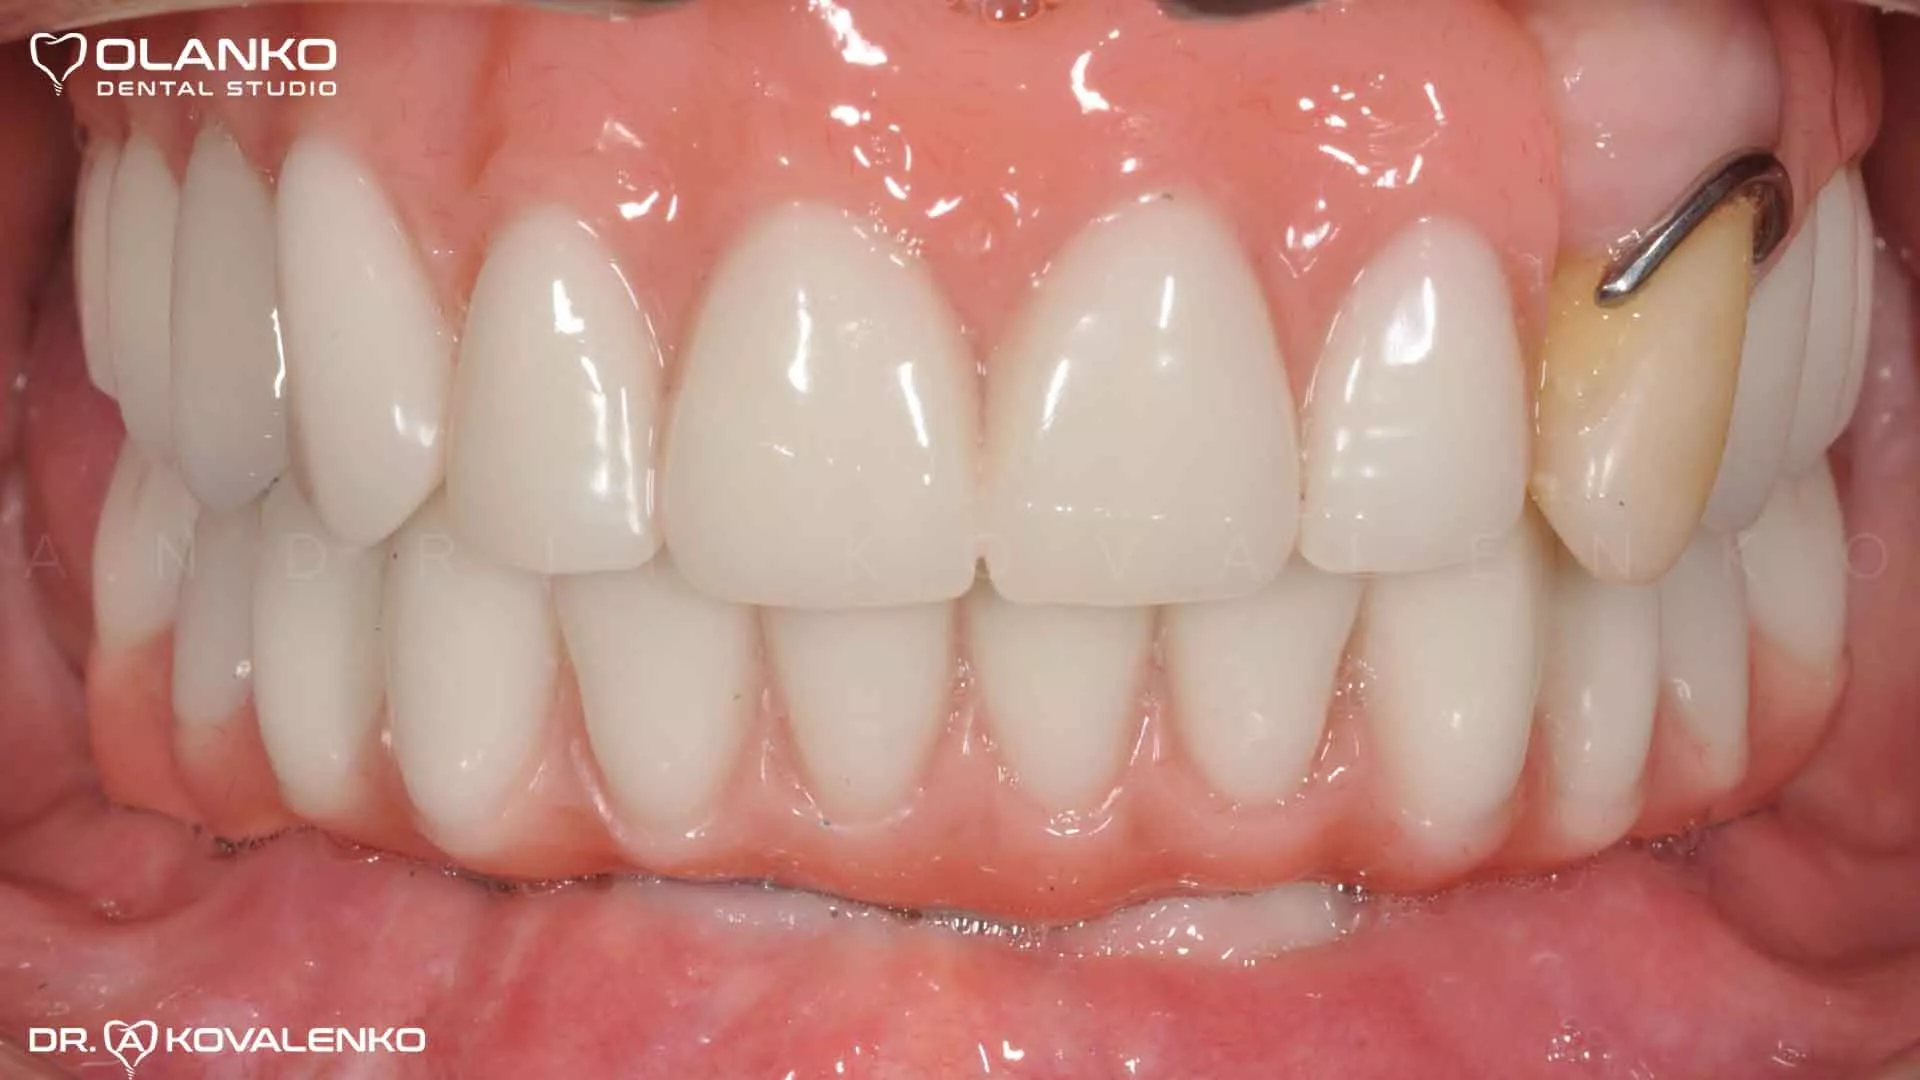

Фото протез установлен прикручен к имплантатам

Клинический случай 9 имплантация зубов